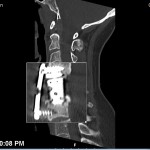

Eight months ago in February 2014, I had my second cervical spine surgery. The neurosurgeon removed a plate and screws that had been put in my neck at the C5, C6 and C7 vertebra to hold a cage and mesh in place that had been put in my neck the previous July during my first cervical spine surgery. The screws had come loose and the plate had slipped, pushing against vocal chords. I had lost my voice which was a part of why I retired in December 2013.

Well, my neck didn’t hurt at first but within a few hours, I began feeling the familiar choking sensation I had experienced when the plate in my neck came loose. It isn’t painful but it is bothersome and uncomfortable. Long story short, I had an X-ray on Monday that showed that there is something out of whack.

I had a CT scan on Friday and will see my neurosurgeon this coming Wednesday and we’ll see what is going on in my neck. In the meantime, the doctor has recommended I wear my neck brace but it makes doing just about everything - especially driving - almost impossible. So I haven’t been very good about wearing it.